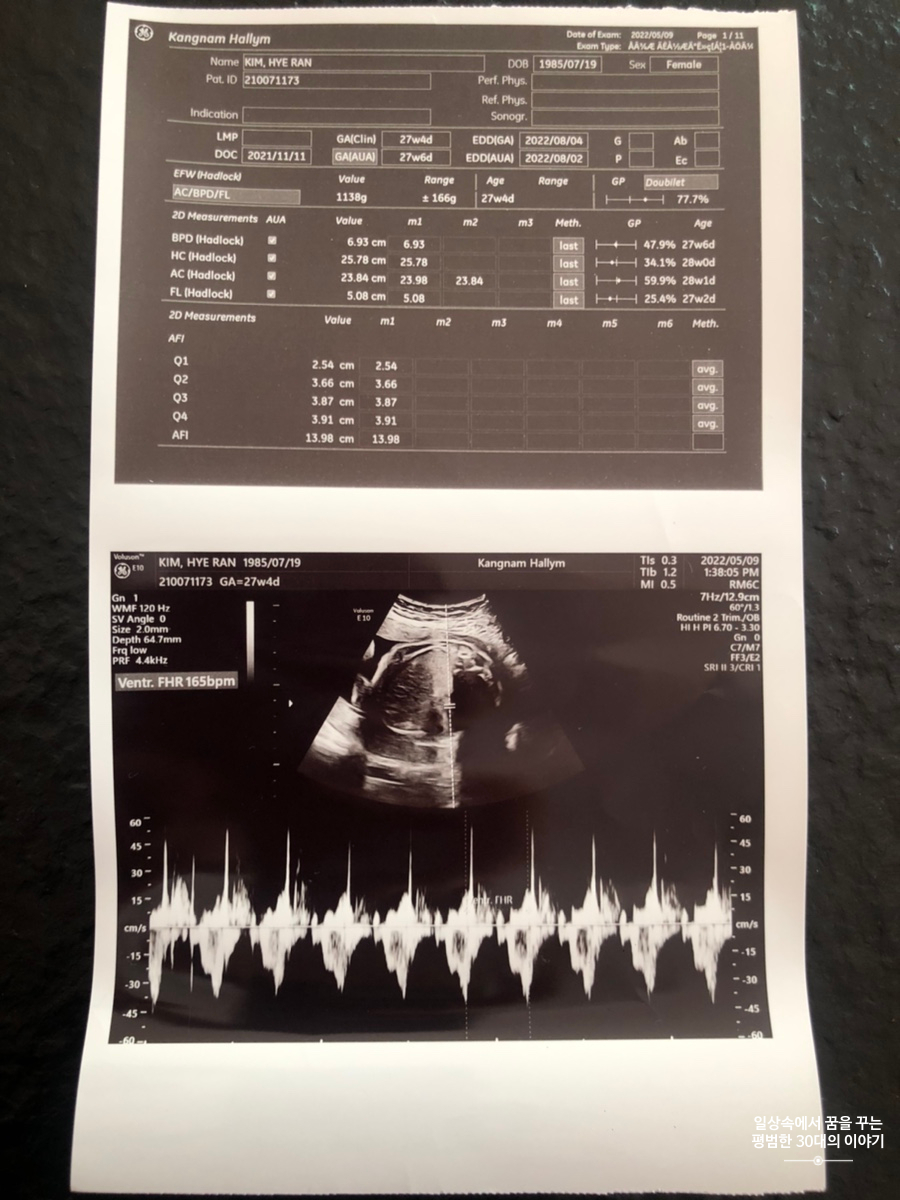

5월 9일 월요일(27주차 4일)

BPD(Biparietal Diameter, 위에서 볼 때 태아 머리 단면의 가장 긴 길이): 6.93cm

HC(Head Circumference, 태아 머리둘레): 25.78cm

AC(Abdominal Circumference, 배 둘레): 23.84cm

EDD(Expected Date of Delivery, 출산 예정일): 2022년 8월 4일

FL(Femur Length, 허벅지뼈 길이): 5.08cm

GA(Gestational Age, 임신 주차): 27주차 4일

EFW(Estimated Fatal Weight, 태아 예상 체중)=EBW(Estimated Body Weight): 1138g

FHR(Fetal Heart Rate, 심장박동 수): 165bpm

CL(Cervical Length, 자궁경부 길이): 4cm

AF(Amniotic Fluid, 양수): 정상